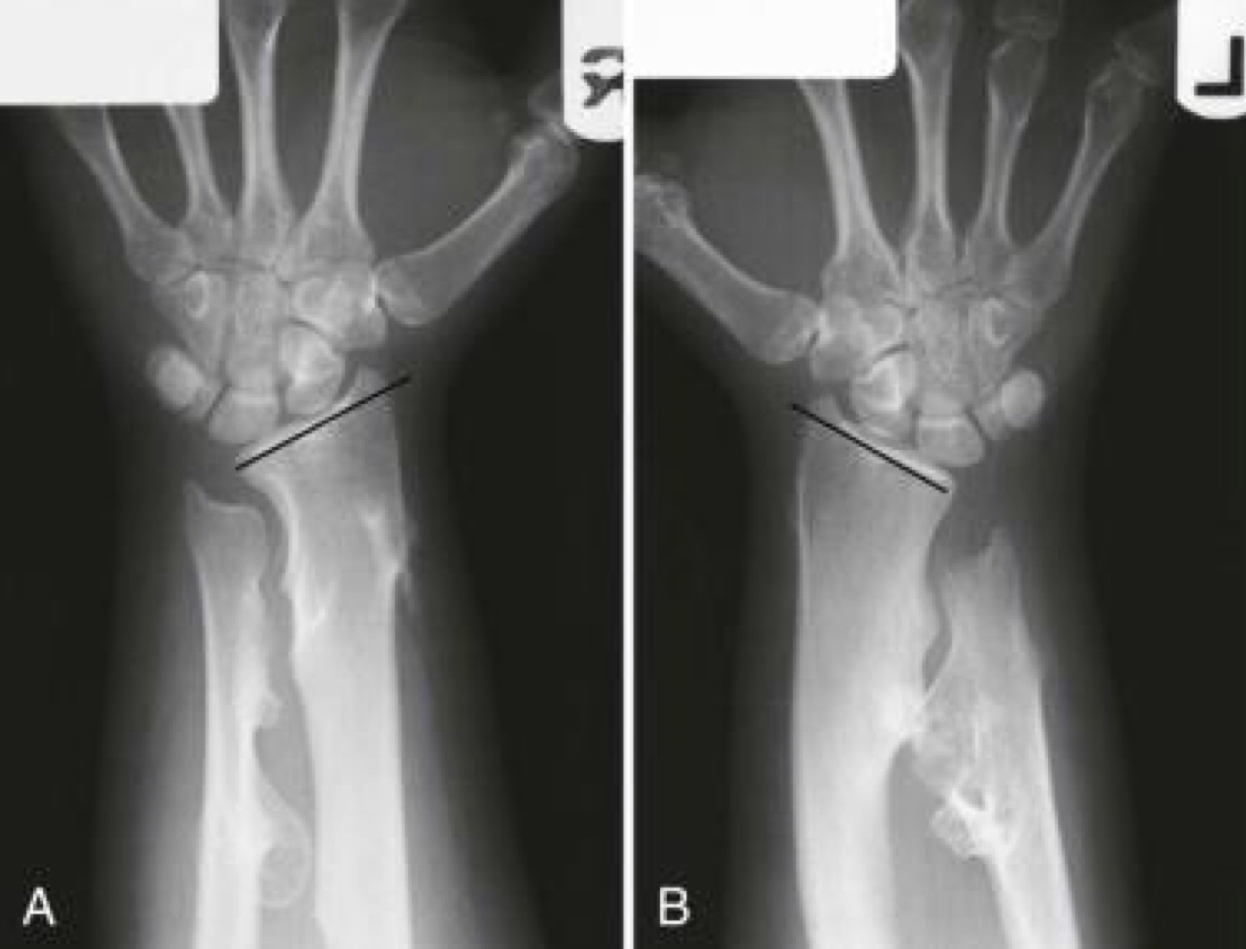

describe this. what is this?

distal radius

extends into subchondral region

diminished bone density

appears aggressive

malignant GCT